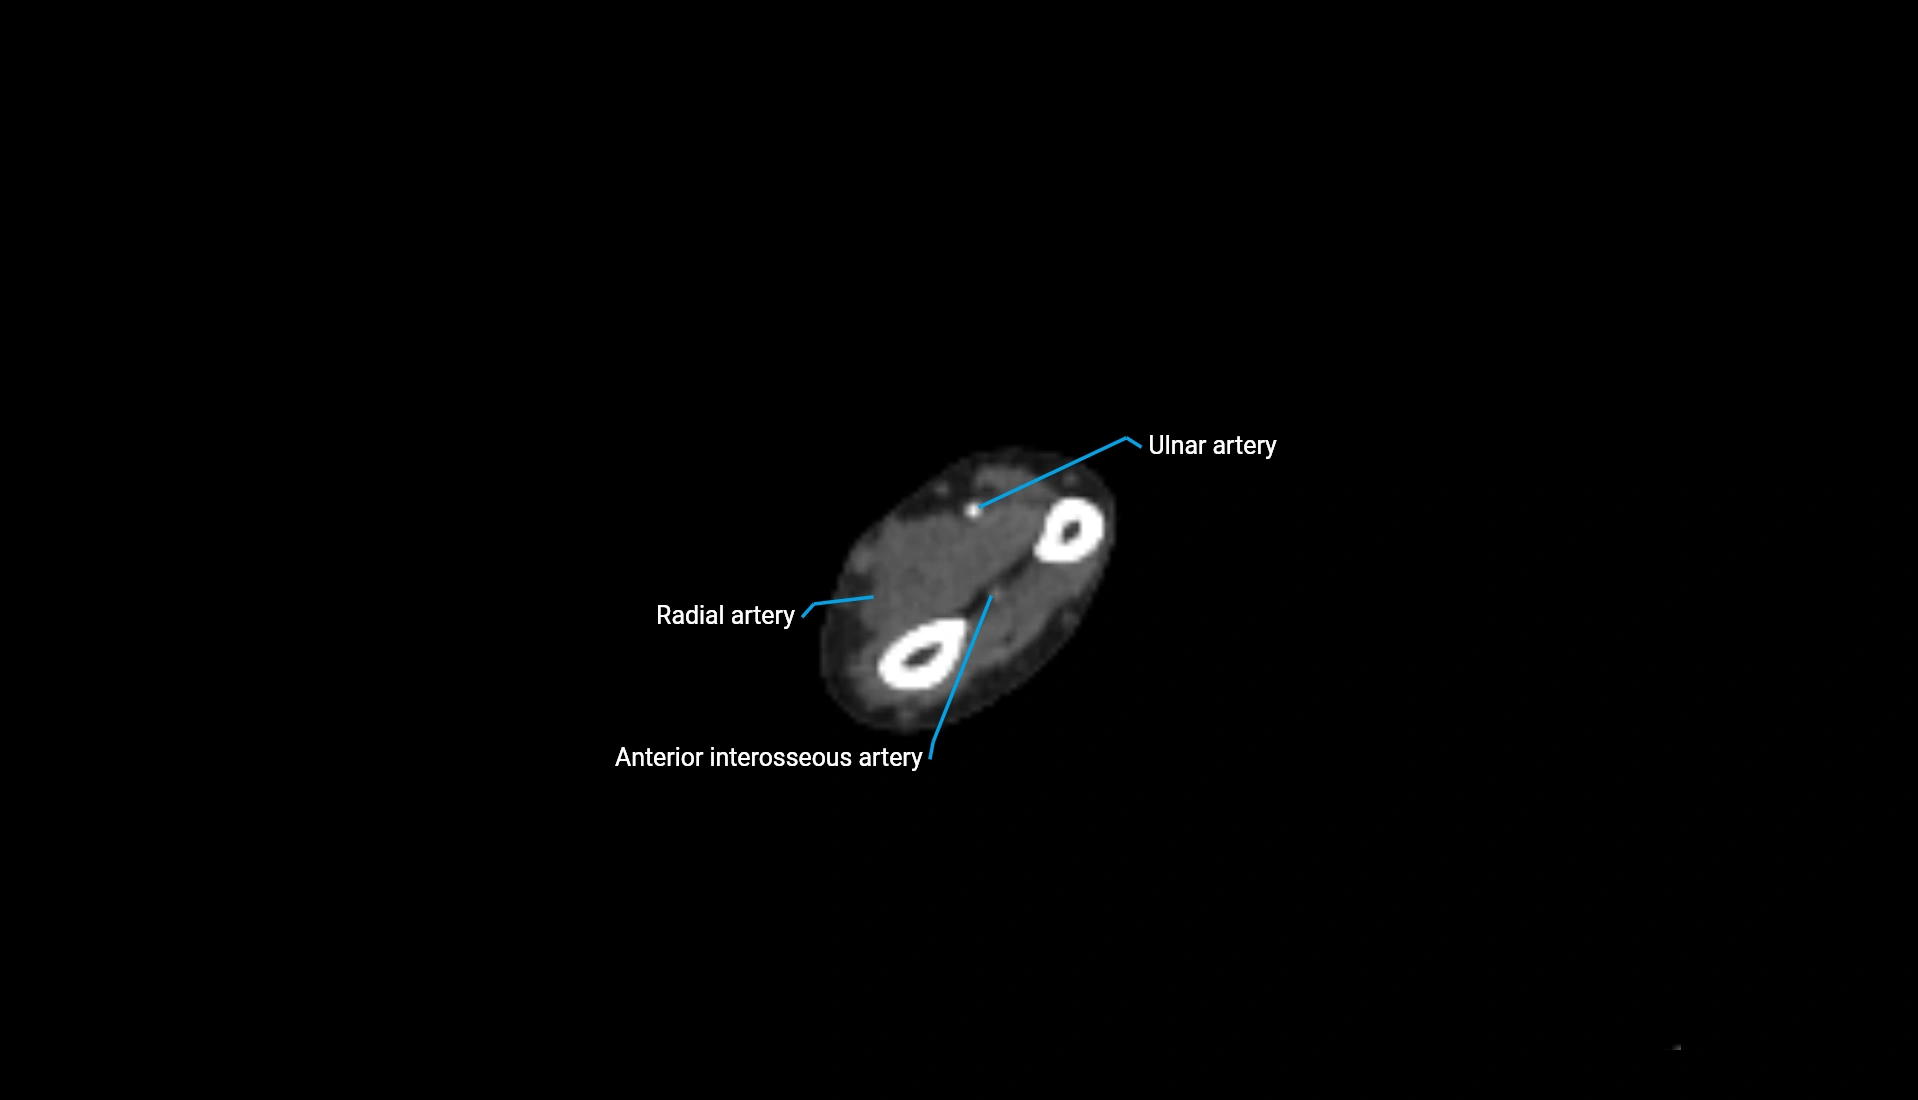

CT Appearance

Non-Contrast CT:

• Cortex: High-density, sharply defined

• Subchondral bone: Dense cancellous matrix

• Articular surface: Smooth concave contour articulating with the capitellum

• Excellent for evaluating bone integrity, alignment, and subtle fractures